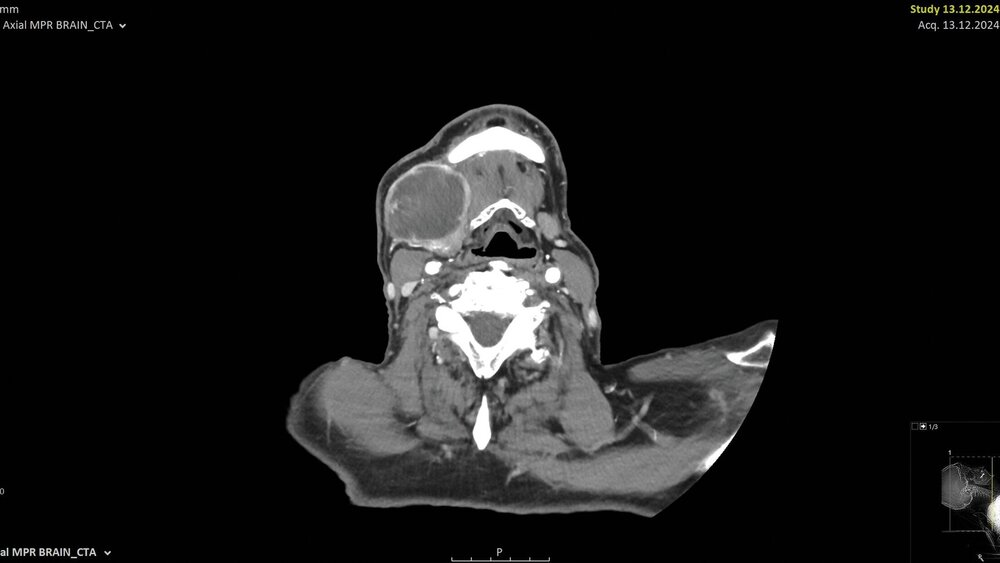

Nach submandibulärer Freilegung der inhomogenen Raumforderung wurden multiple Proben entnommen. Im Verlauf der Exzision entleerte sich eine hornartige Substanz (Abbildung 2). Die intraoperative Schnellschnittuntersuchung ergab in sämtlichen Proben die Manifestation eines mäßig differenzierten, verhornten Plattenepithelkarzinoms mit ausgeprägter chronisch-resorptivzelliger Entzündung und Fremdkörperreaktion. Daher erfolgte die Resektion der Raumforderung mit adäquatem Sicherheitsabstand unter Mitnahme der adhärent wachsenden Hautanteile in toto (Abbildung 3). Zusätzlich wurde eine selektive Neck Dissection der Level II–IV durchgeführt. Der entstandene Defekt wurde unter Berücksichtigung der funktionellen und ästhetischen Aspekte mittels eines freien, mikrovaskulär anastomosierten anterolateralen Oberschenkellappens (ALT-Lappen) rekonstruiert (Abbildung 4).